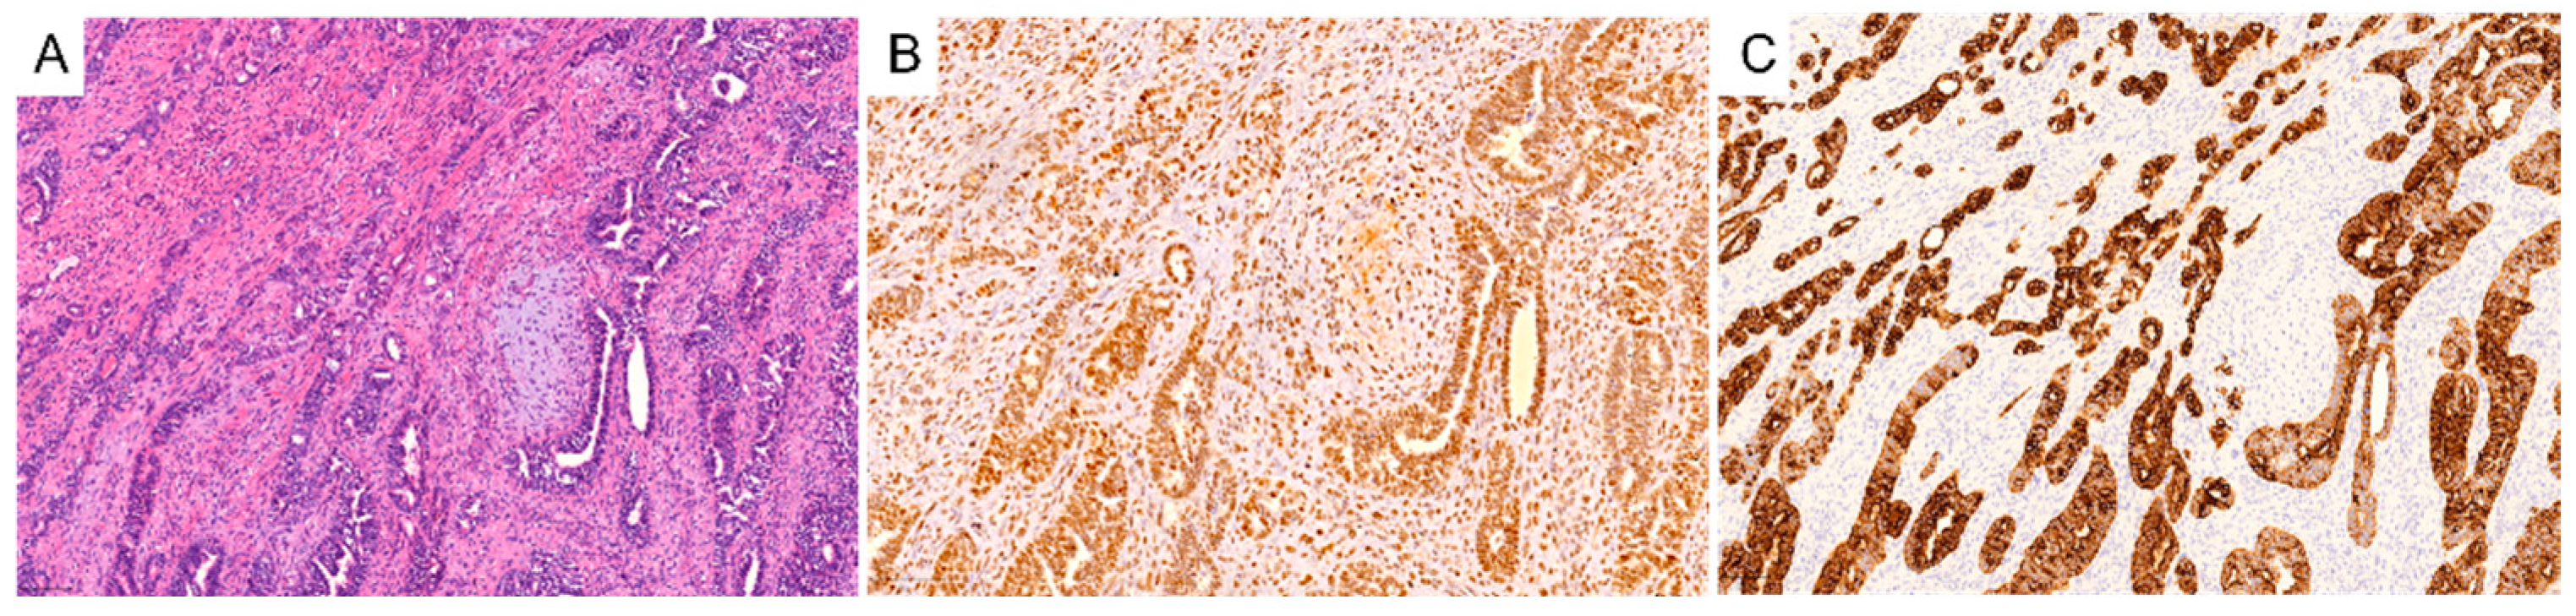

3. Immune Microenvironment in Carcinosarcoma